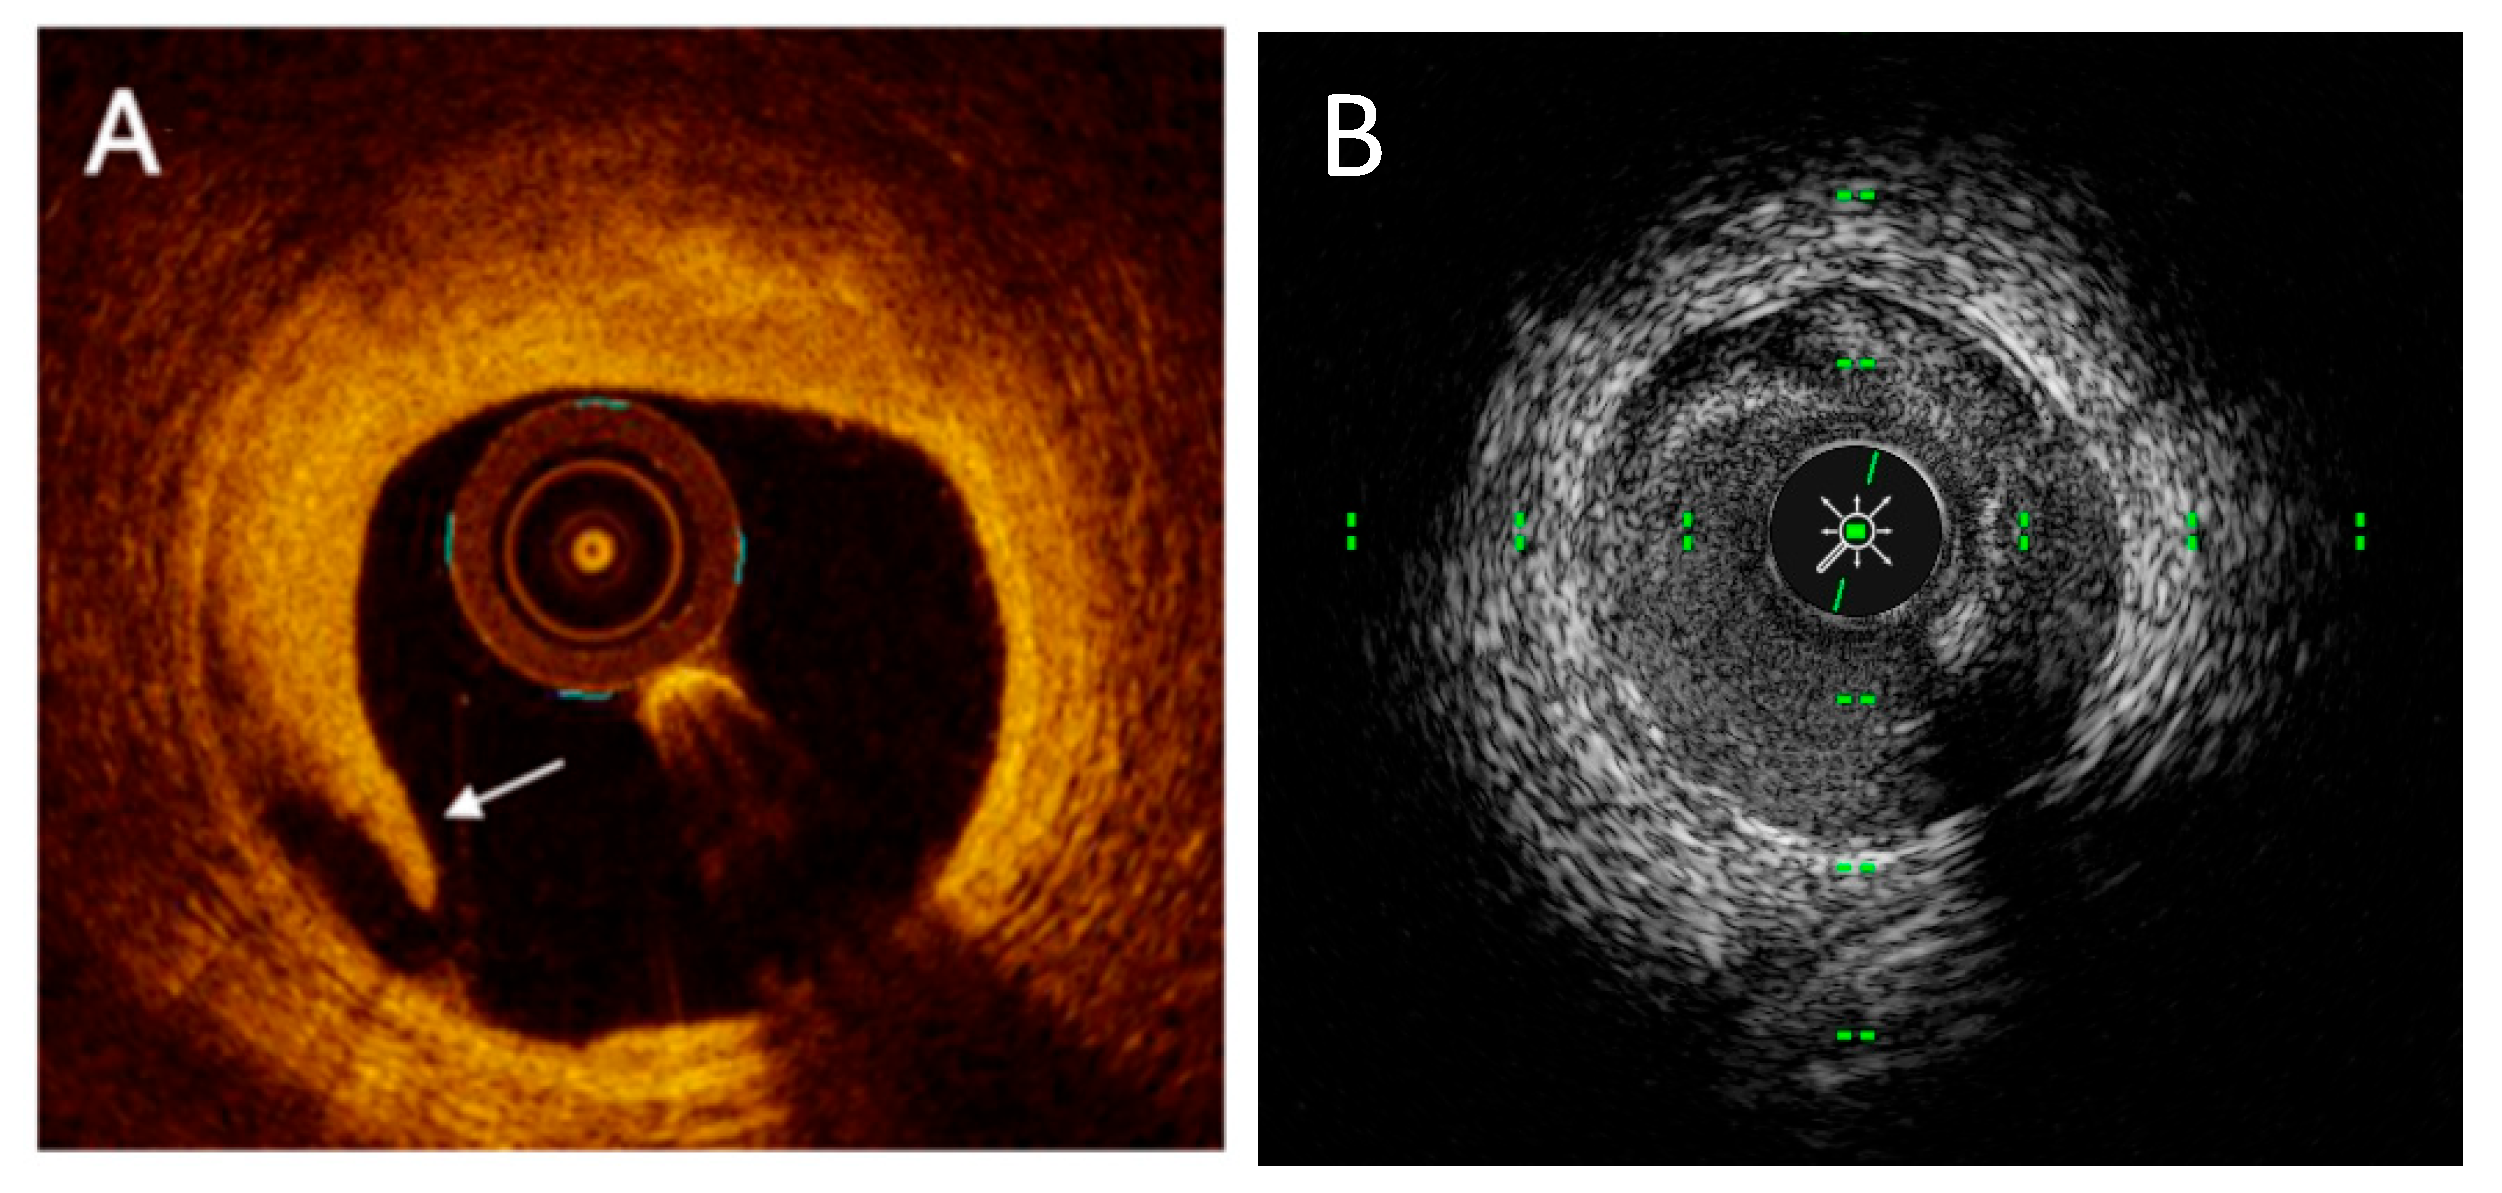

1. Introduction

2. Intravascular Imaging Technology

2.1. IVUS Technology

2.2. OCT Technology

6.1. NIRS